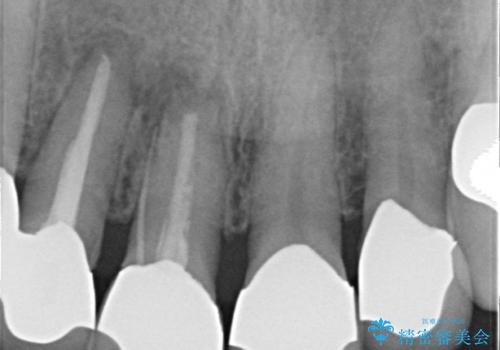

- 前歯の痛み・排膿・ぐらつきの改善を求めて来院されました。

視診・X線写真検査より根尖性歯周炎が認められ再治療が必要な状態です。

再根管治療を行うべくクラウン除去を行ったところ、右上側切歯に保存不可能な垂直性の破折が認められたため抜去が必要になりました。

即切歯の抜歯を行う場合犬歯を含めたブリッジによる補綴計画を立てることが多いですが、今回は犬歯から大臼歯にかかる大きなブリッジが既に装着されていたため予算とご希望を相談し前歯のみの延長ブリッジ補綴で治療を行っていくこととしました。